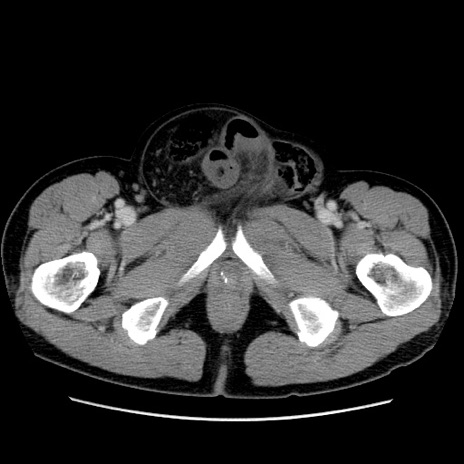

症例34(横断像)

【症例】60歳代 男性

【主訴】右鼠径部膨隆

【現病歴】1年程前より右鼠径部膨隆あり。自己にて還納可能だったため放置していた。3時間前より右鼠径部の脱出を認め、還納困難となり受診。

【既往歴】高血圧

【身体所見】右鼠径部に小児頭大の膨隆あり。弾性硬であり、用手還納は困難。左鼠径部にも膨隆を認める。脱出はなし。